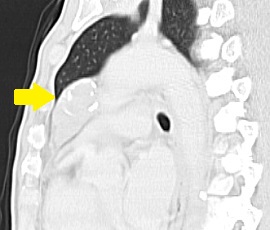

[胸腺腫] 手術:胸腔鏡下縦隔腫瘍手術

CT画像